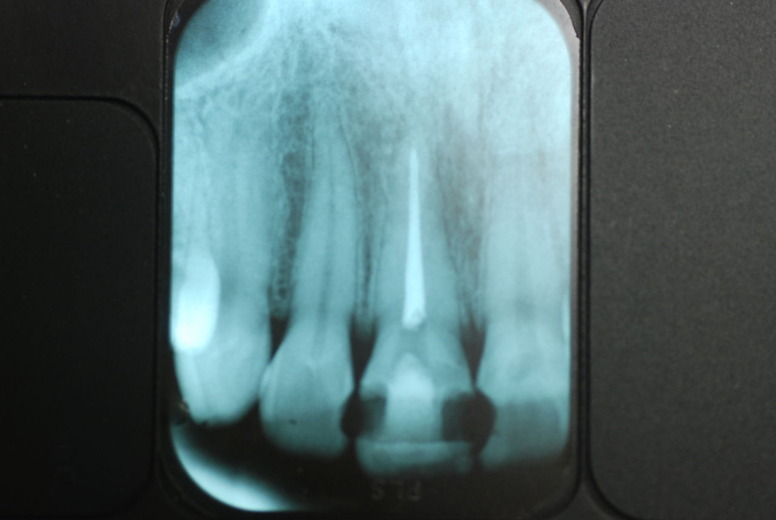

14年歯前、歯の神経が腐り、神経を除去したまま来なくなった現在大学生の女性

歯周病になっていましたが、少し色が黄色くなっているだけで比較的綺麗な歯の状態です。

平成9年来院神経を取り、同時に歯周病の話をしてそのまま来なくなっていたかたですが、たまたま一部欠けてきました。それで来院。

平成24年一部欠けて来院

15年前と同じように詰めて終了。磨き方はまあまあでした。でも問題少ないでしょう。![ea7f9628-s[1]](https://livedoor.blogimg.jp/netdental/imgs/c/2/c2ef91be.jpg)

虫歯という病気を完全に治し、神経の処置で神経の病気を治し、ブラシの使い方をマスターすれば歯やお口の中は問題を起こしにくいのです。何かを被せることは注意が必要ですし、歯を傷つける訳ですからブラシの使い方をマスターしてから被せないと危ないのです。